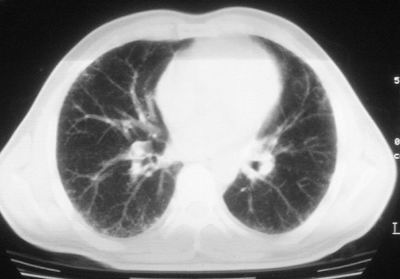

患者,男,44岁,糖尿病4年余,近期消瘦、乏力。化验检查:总胆红素26.33(参考值:5.1-17.2u mol/l),直接胆红素:6.4(参考值:0-4.3u mol/l),谷-丙转氨酶(alt):843(参考值:<40u/l),hbsag(+),抗hbs(-),hbeag(-),抗-hbe(+),抗-hbc(+)。

1\\粟粒性肺结核可能性大,支气管肺泡癌不排除

双肺散在小结节影,考虑粟粒性肺结核.肺窗薄扫会更好看些.

双肺外侧带胸膜下可见网状阴影,考虑轻度肺间质纤维化。

双肺纹理增强并可见网格状影达外带,考虑双肺感染并轻度间质纤维化

1.双肺急性粟粒型肺结核;2.少量腹水.

肺间质纤维化并肺部感染,结合不能排出,毕竟糖尿病人易合并之,建议结合ppd检查或hrct进一步扫描。